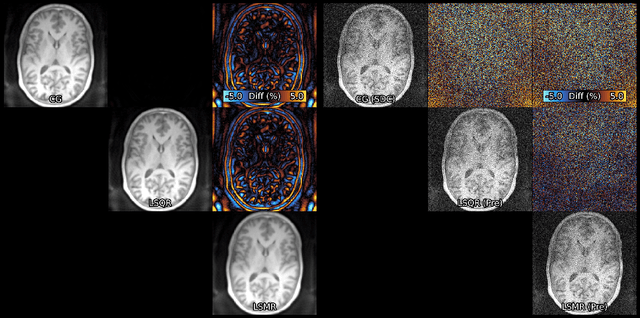

Figure 1 for Algorithms for Least-Squares Noncartesian MR Image Reconstruction